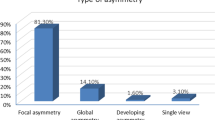

Regarding Mammographic findings in our study, the type of asymmetries was assessed; 43/51 (84.3%) of the asymmetries were focal asymmetry, 1/51 (2.0%) were asymmetry, and 7/51 (13.7%) were global asymmetry. One or more associated mammographic findings were detected as shown in Table 3